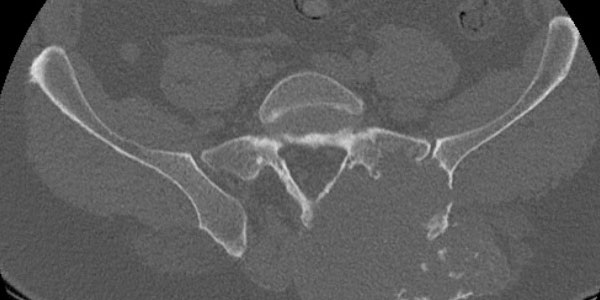

Chondrosarcoma is a malignant tumor of the bone that originates from cartilage tissue. Chondrosarcoma usually occurs after the age of 40 and is more common in men.